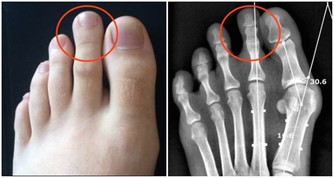

“空調腿”是指室內開啟空調後,地面水平溫度最低,人的雙腿長期低暴露在外,

容易受涼刺激,出現雙腿酸痛,嚴重時膝關節疼痛、腫脹,使人難以忍受。

絕大多數“空調腿”是膝關節受寒冷刺激導致的滑膜炎、滑囊炎以及腿部肌肉受冷痙攣。